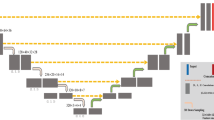

Architecture of the 3D U-net. Patch size of 112 × 96 × 224 with batch size 2 is fed to the neural network. Weights are updated with the rectified Adam optimizer. (PPTX 109 kb)